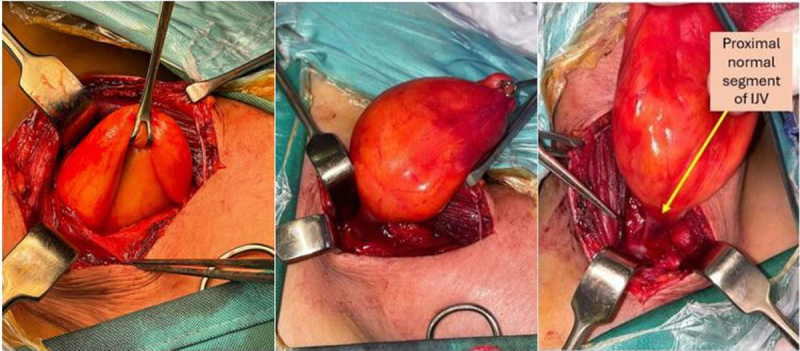

A 25-year-old female presented with a congenital painless growing mass on the right side of her neck with symptoms of tinnitus and difficulty breathing. Imaging revealed an aneurysm of the internal jugular vein reaching a maximum diameter of 9.2 cm, shifting the trachea and right thyroid lobe to the left side. Simple excision was sufficient to treat compression symptoms and prevent potential thrombosis and embolism. This is the first reported case of aneurysmal internal jugular vein with fibrofatty degeneration and hamartomatous wall morphology associated with compression symptoms.

25岁女性,颈部右侧先天性无痛性生长肿块,伴有耳鸣和呼吸困难。影像学显示颈内静脉动脉瘤最大直径达9.2 cm,气管和右甲状腺叶向左侧移位。单纯的切除足以治疗压迫症状,防止潜在的血栓形成和栓塞。这是首次报道的动脉瘤性颈内静脉纤维脂肪变性和错构瘤壁形态与压迫症状相关的病例。